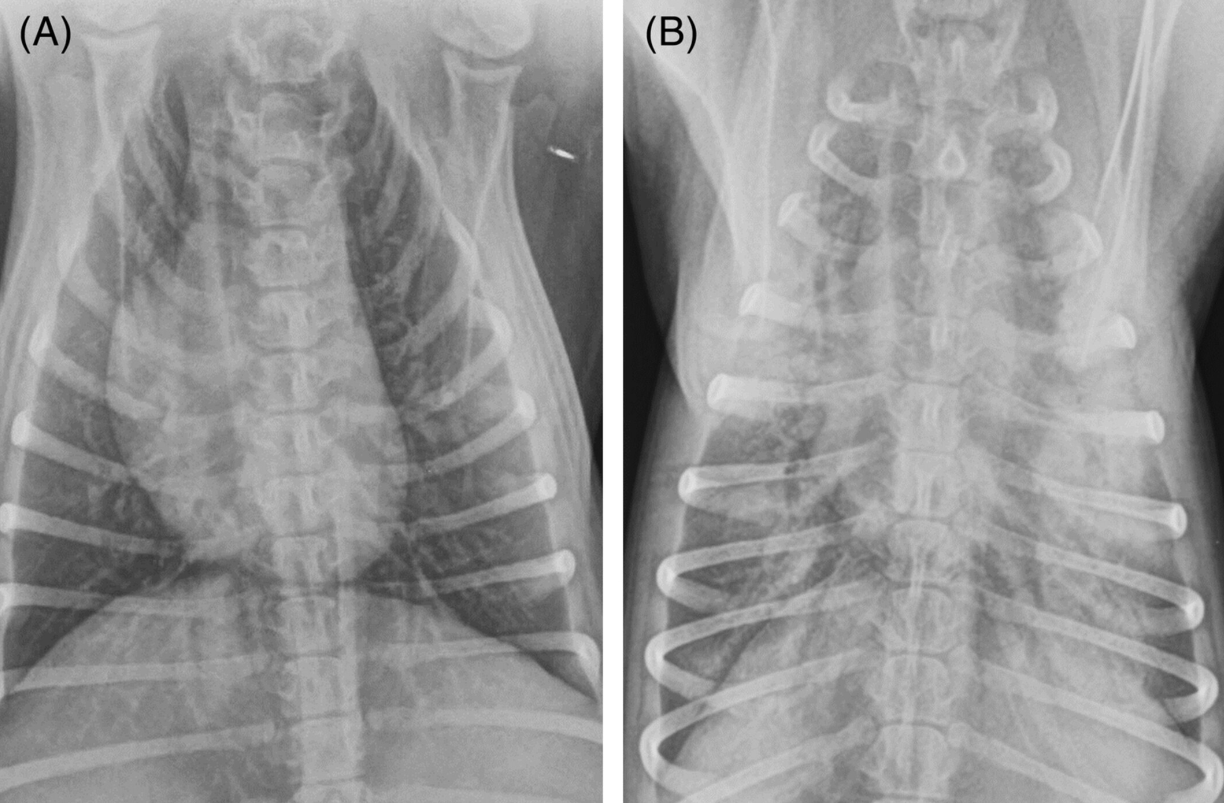

신경의 과흥분 상태와 심장 박동의 폭발적 항진으로 인하여 폐수종이 발생할 수 있다. 사람, 경주마, 사냥개에서 이미 오래전부터 보고되어 있던 케이스에 대한 보고이다.

실제로 필드에서 "어제까지는 공원에서 비숑타임도 갖고 너무 잘 뛰어놀았는데 왜 이러나?"라는 보호자의 불만 섞인 하소연을 종종 들어볼 수 있는데 이들이 이런 과흥분상태에 의한 폐수종 가능성이 있는 환자로 생각된다.

물론 모든 비숑타임 후 폐수종이 발생한다는것은 아니다. 다만 비숑타임이나 과흥분 상태 이후에 호흡이 나빠지면 최대한 빠른 시간 내에 동물병원에 들고뛰라는 근거가 될만하여 소개한다.